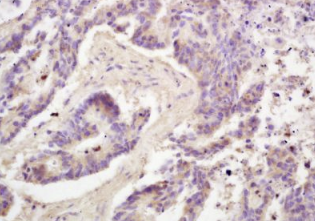

组织/细胞:人结肠癌;4%多聚甲醛固定石蜡包埋;

抗原提取:柠檬酸缓冲液(0.01M,pH 6),15min煮沸,用3%过氧化氢阻断内源性过氧化物酶30min;37℃下阻断缓冲液(正常山羊血清)20 min;

孵育:抗脂联素多克隆抗体,未结合1:200,在4°C下过夜,然后接合二级抗体和DAB染色。